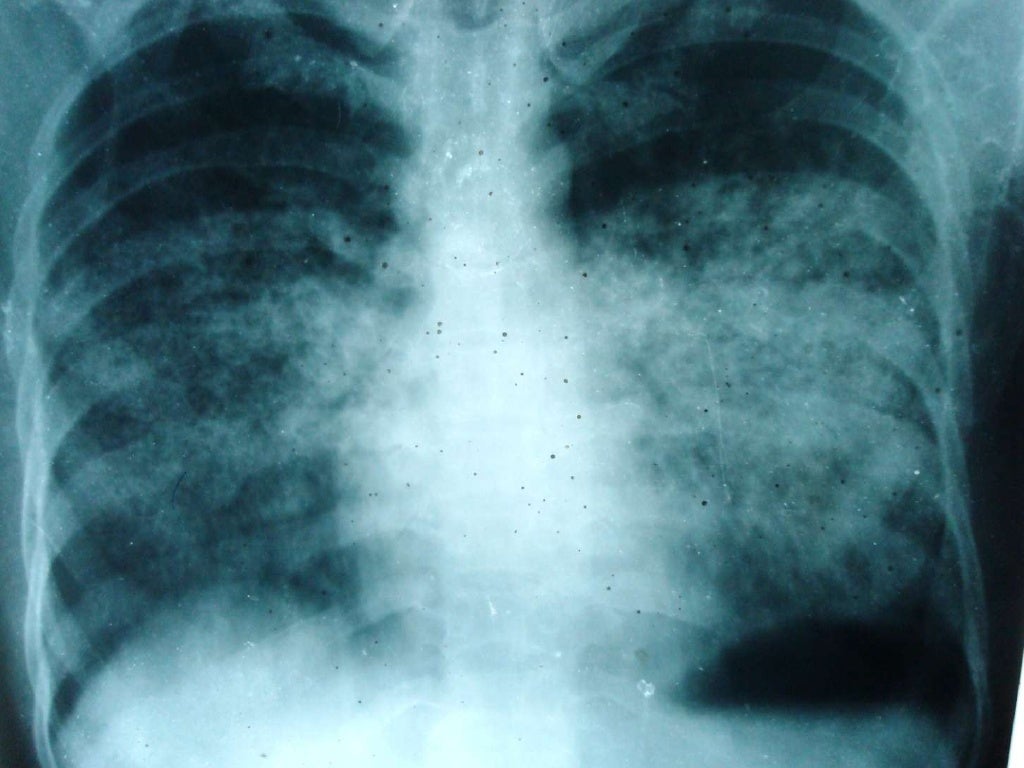

Chest X Ray Pneumocystis Carinii Pneumonia . The purpose of this study was to compare the time course of clinical and radiographic improvement in patients with pneumocystis. Multiple ill defined small hyperlucent patches are noted in the bilateral lung fields especially in the mid zones suggestive of pneumatocele.

The purpose of this study was to compare the time course of clinical and radiographic improvement in patients with pneumocystis. Multiple ill defined small hyperlucent patches are noted in the bilateral lung fields especially in the mid zones suggestive of pneumatocele.